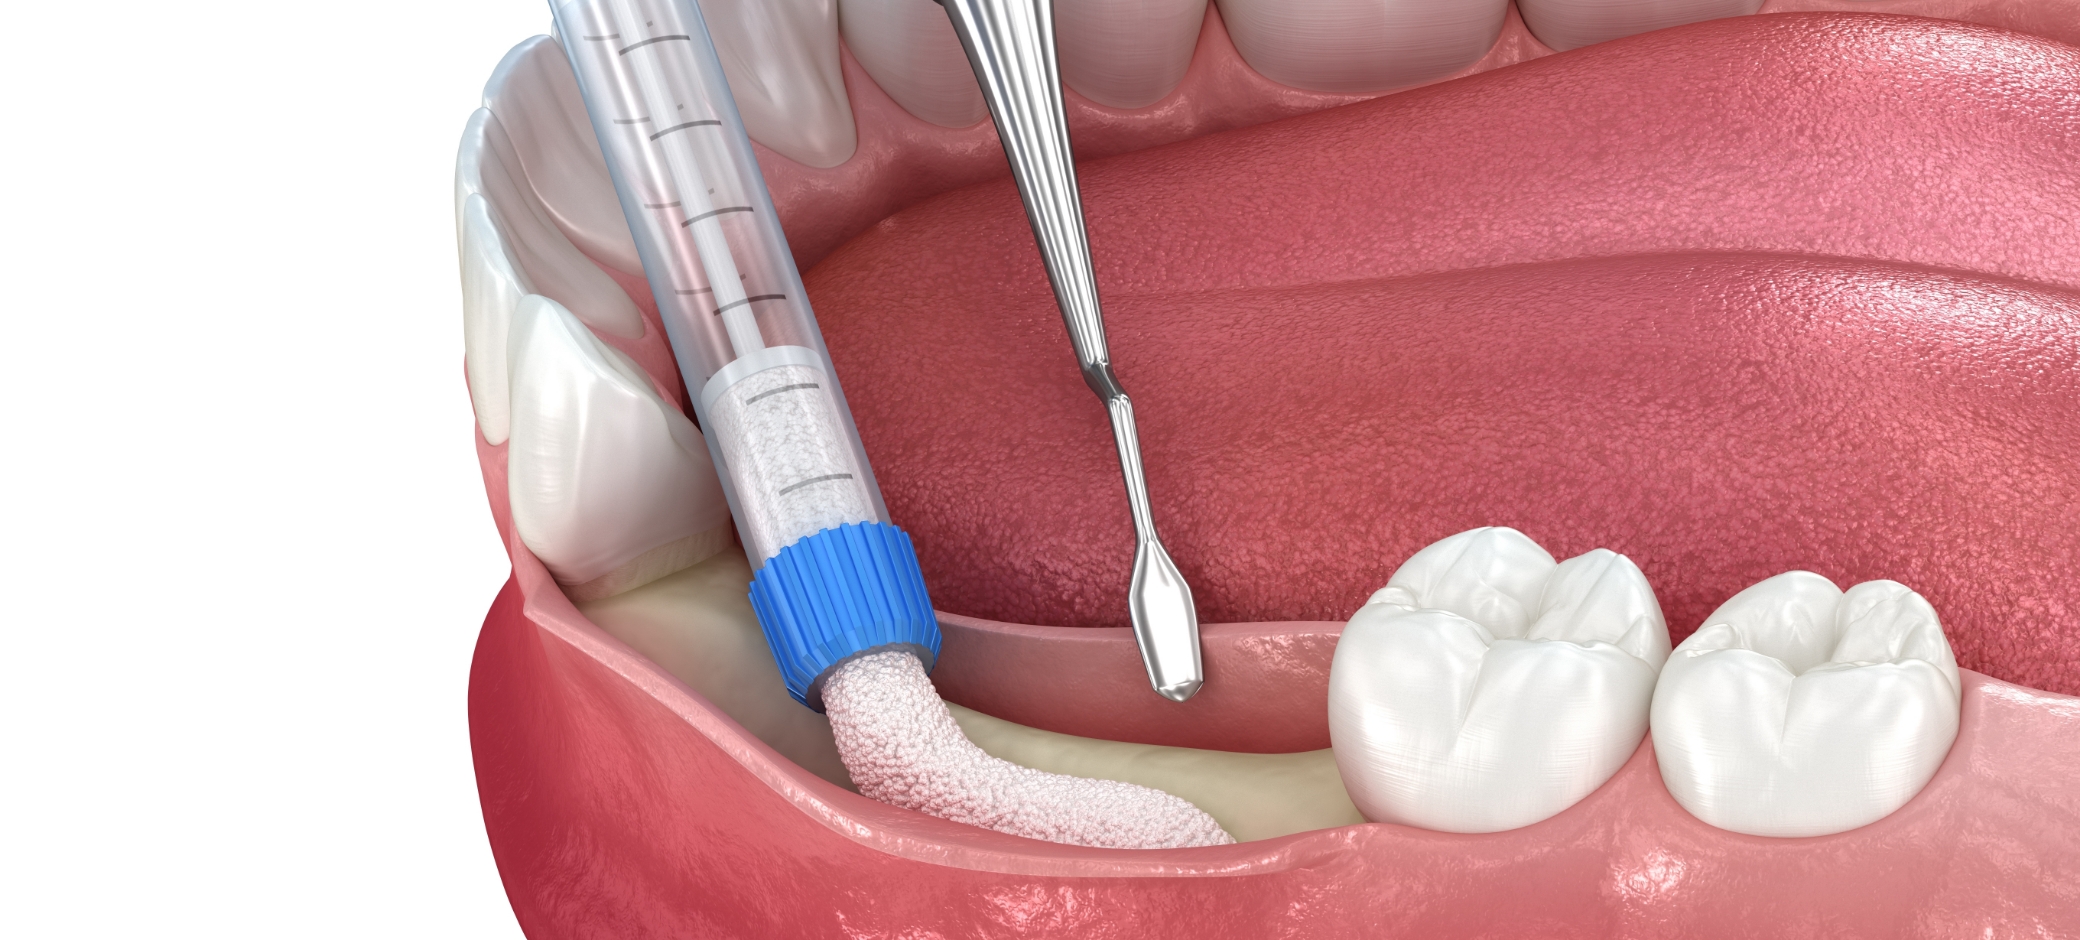

• 잇몸뼈이식

뼈이식재를 통해

부족한 잇몸뼈를 보완

• 2. 잇몸뼈이식